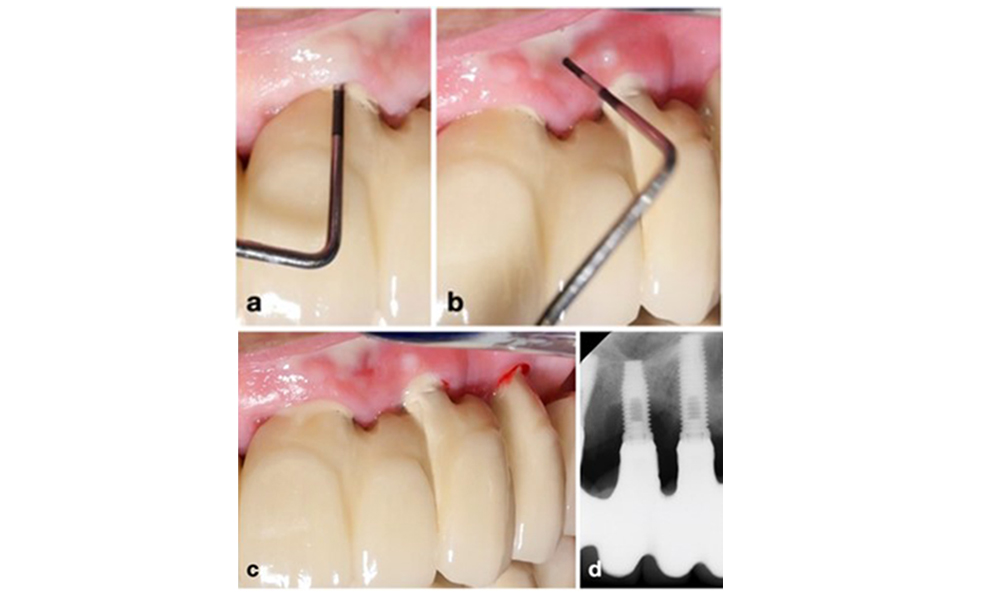

La péri-implantite est identifiée par (1) des signes d'inflammation similaires à la mucosite, (2) des preuves radiographiques de perte osseuse après la cicatrisation initiale et (3) une augmentation de la profondeur de sondage par rapport aux mesures prises peu après la mise en place de la reconstruction prothétique (figure 2). En l'absence de radiographies antérieures, un niveau osseux radiographique de ≥ 3 mm, accompagné d'un saignement au sondage et d'une profondeur de sondage ≥ 6 mm, indique une péri-implantite.

La perte osseuse attendue après la cicatrisation initiale, attribuée au remodelage de l'os marginal, varie en fonction de facteurs tels que le système ou le type d'implant. Par exemple, une perte osseuse de 1 à 2 mm est généralement considérée comme "normale" pour les implants au niveau de l'os avec une connexion externe (figure 2d, implant en position 23).